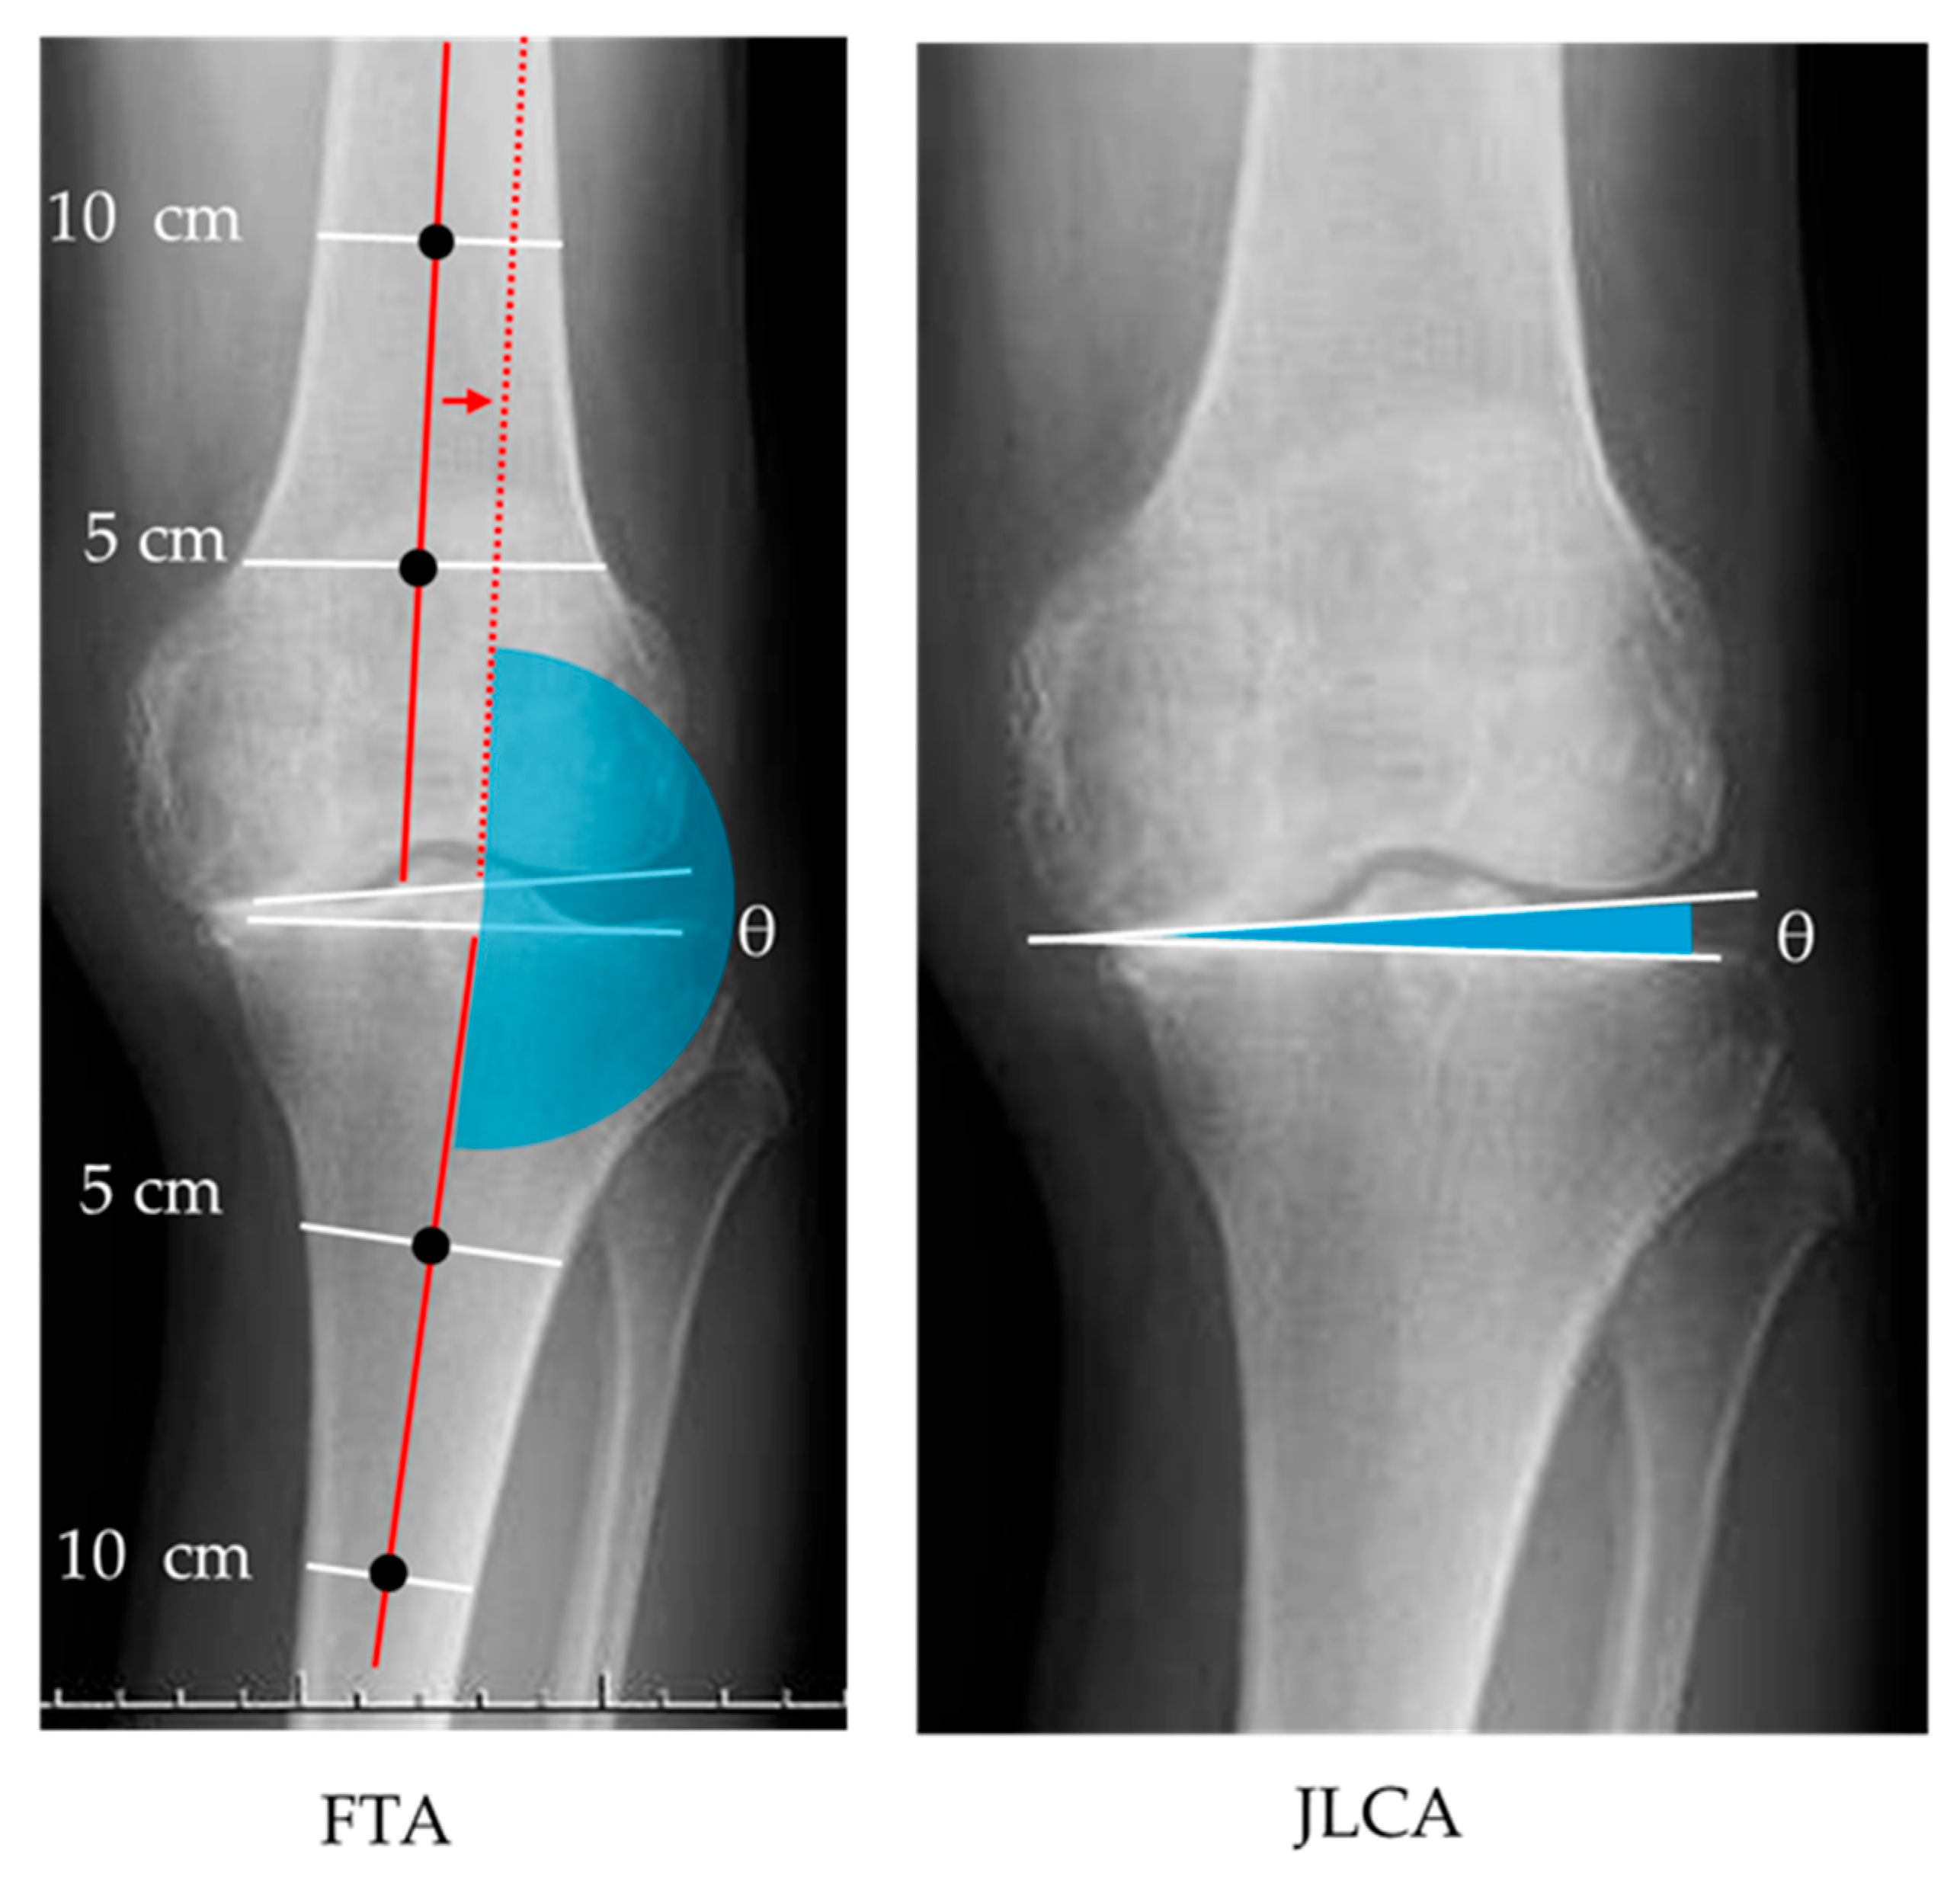

2.3.2. Radiographic Images

| FTA (°) | 179.6 | ± | 4.1 |

| JLCA (°) | 3.1 | ± | 3.0 |

| FTA | JLCA | |||||

|---|---|---|---|---|---|---|

| ρ | 95% CI for ρ | p-Value | ρ | 95% CI for ρ | p-Value | |

| Standing TA | 0.47 | 0.07, 0.76 | 0.04 | 0.80 | 0.29, 0.92 | <0.01 |